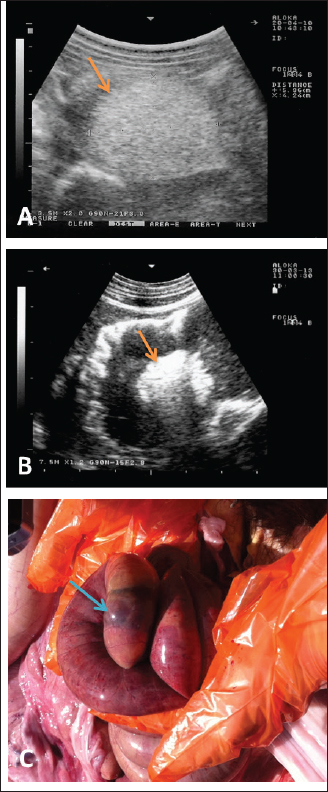

Fig. 6. Ultrasonographic findings in camels with depraved appetite. In image (A), a wool ball (5.4 × 4.2 cm) was detected obstructed the small intestines in an adult male camel (arrow). Image (B) shows a foreign body detected within the small intestines in a 5-day female camel calf (arrow). Images were taken from the right lower abdomen using 3.5 and 7.5 MHz sector transducers, respectively. Image (C) shows the obstructing wool ball detected at necropsy of the camel shown in Fig. 6A.

During the past 13 years, our research group has focused on the effectiveness of diagnostic imaging techniques in dromedary camels either in the healthy or diseased conditions (El-Tookhy and Tharwat, 2012; Ali et al., 2018; Al-Sobayil et al., 2018; Tharwat et al., 2012a,b,c,d; Tharwat, 2013a; Tharwat et al., 2013; Tharwat and Al-Sobayil, 2016a; Tharwat et al., 2018a; Tharwat, 2019; Tharwat, 2020a,b,c; Tharwat, 2021a,b; Tharwat and Al-Hawas, 2021; Tharwat and El-Tookhy, 2021; Tharwat et al., 2021; Tharwat and Al-Hawas, 2023; Tharwat et al., 2023; Tharwat,$ 2024; Tharwat and Al-Hawas, 2024). In these studies, the occluding foreign body was imaged obstructing the intestines either partially or completely. Because of the gaseous contents, the foreign bodies could not be localized within the rumen. However, in camels with rumen sand impaction, shining pin-points with acoustic enhancement are clearly visualized.